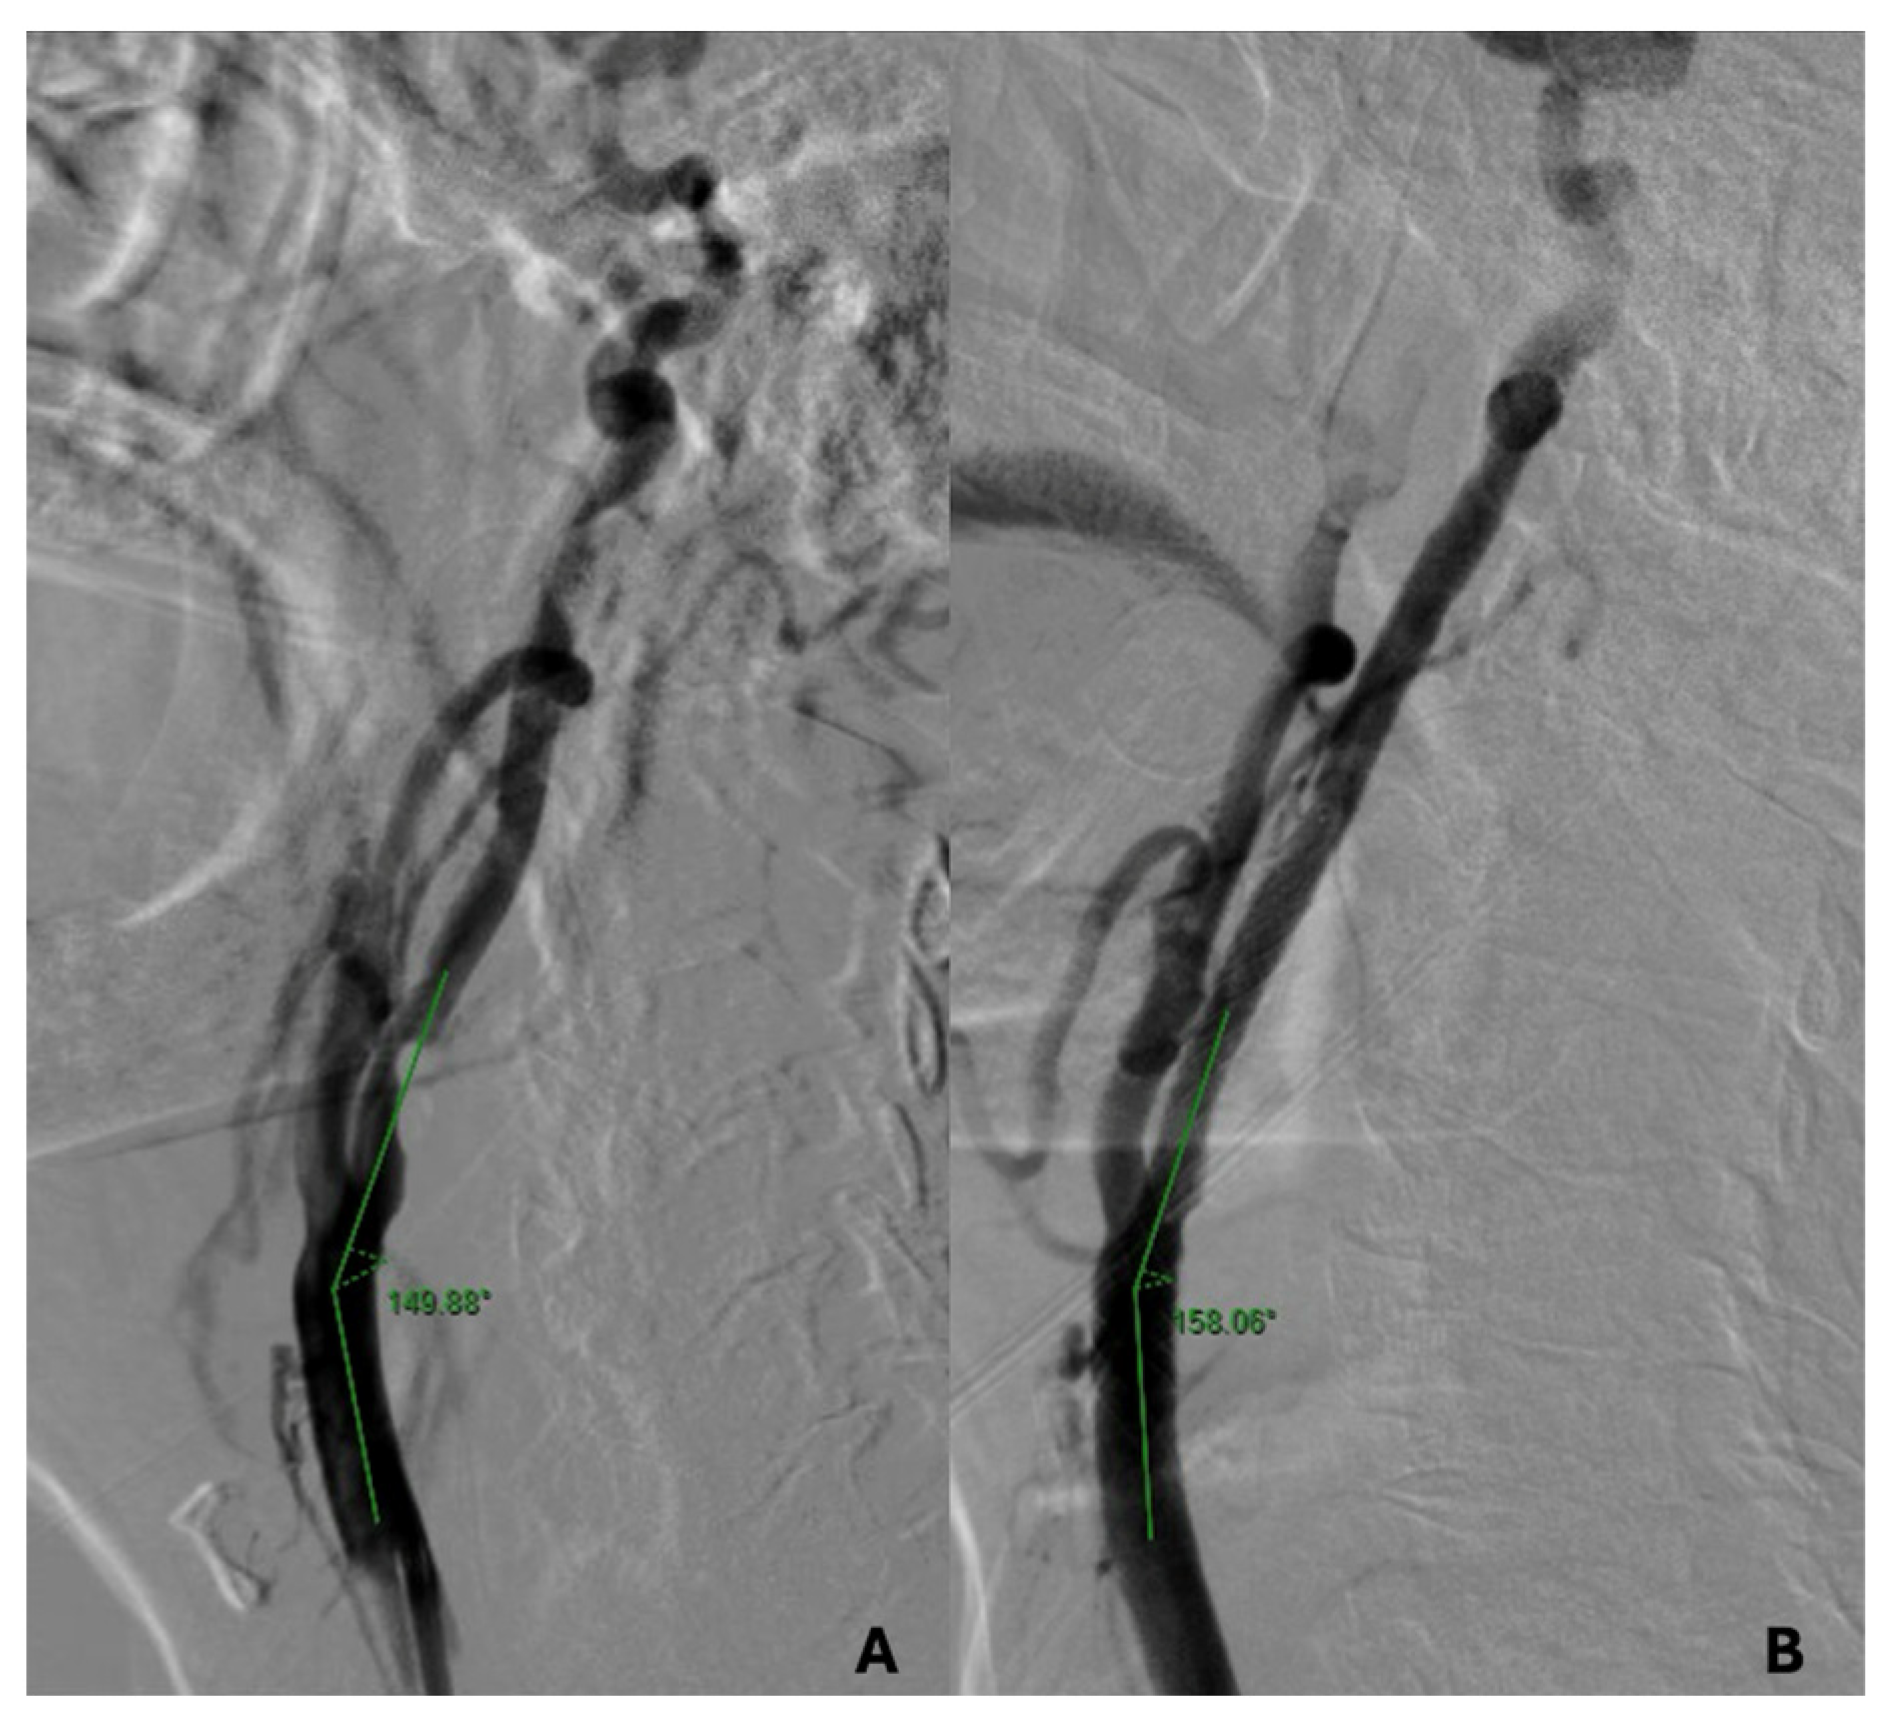

| Pre-stenting CCA-ICA angle | 155 ± 14.9 | 156.8 ± 13.8 | 149.7 ± 14.8 | 156.5 ±16.9 | 0.6 |

| Post-stenting CCA-ICA angle | 167.7 ± 8.7 | 169.6 ± 7.1 | 165.8 ± 8.4 | 164.2 ± 11.9 | 0.5 |

| p value | 0.0001 | 0.0001 | 0.0001 | 0.02 |